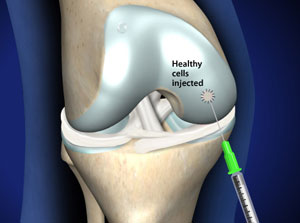

Bei der klassischen ACT näht der Orthopäde einen körpereigenen Knochenhautlappen auf den vorbereiteten Defekt wasserdicht auf und injiziert in diesen entstandenen Hohlraum die gezüchteten, körpereigenen Knorpelzellen.

Bei der autologen dreidimensionalen Knorpelzelltransplantation (autologe matrixinduzierte Chondrozytentransplantation, kurz ACT 3D) werden dreidimensionale Knorpelzellkügelchen (Sphäroide) ohne Notwendigkeit einer Abdeckung auf den vorbereiteten Defekt aufgebracht. Der Eingriff erfolgt in unserer Klinik per Miniarthrotomie unter arthroskopischer Sichtkontrolle. Dieses minimalinvasive Verfahren gewährleistet eine maximal schonende Behandlung des paraartikulären (um das Gelenk gelegenen) Gleitgewebes und vermindert die Operationsrisiken wesentlich.

3. Schritt: Implantation der Knorpelzellen

Sobald die Knorpelsphäroide mit dem vorbereiteten Knorpeldefekt Kontakt aufnehmen, heften ihre 'Verbindungsmoleküle' (Adhäsionsproteine) innerhalb von ca. 10 Minuten mechanisch stabil am Knochen. In der Folge wachsen die Knorpelzellen in den Defekt ein, bis dieser komplett ausgefüllt wird.

Dieser Eingriff erfolgt in der Gelenk-Klinik minimalinvasiv unter arthroskopischer Sicht und dauert etwa 30–60 Minuten. Dabei entfernt der Orthopäde zunächst das geschädigte Knorpelgewebe und bringt dann die gezüchteten, körpereigenen Knorpelzellaggregate ein. Durch das spezielle Züchtungsverfahren haften die Knorpelzellen an.